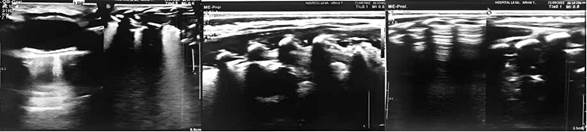

Cuenta con una biometría hemática dentro de parámetros normales, grupo “A” RH (+), cursa no rmoglucemia, bilirrubinastotalesa predominio indirecto sin criterios de luminoterapia con tiempo de protrombina prolongado. Se indica el oxígeno suplementario (Halo cefálico) y un plan de hidratación parenteral. Para completar el estudio se realiza una ecografía toracoabdominal que identifica el paso de asas intestinales al tórax derecho, sin herniación de vísceras sólidas. (Fig. 2).

Figura 2. Ocupación de hemitórax derecho por estructuras aéreas que corresponden a asas intestinales en relación con una hernia diafragmática.